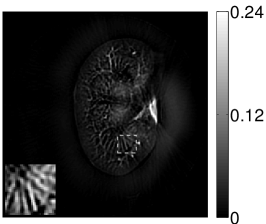

VI-E Results: kidney phantom

The images and EIRs reconstructed by use of the VP algorithm that was based on the 2D imaging model that neglected the SIR are shown in Figures 15 and 16. The latter figure contains results corresponding to different values for the regularization parameter . From Fig. 15, it can be observed that use of the conventional iterative method that utilized the measured EIR resulted in distortions and loss of details in the reconstructed images. Use of the VP algorithm improved the contrast and the details in the reconstructed images (Fig. 15(c) and 16(a)). Furthermore, the images reconstructed by use of the VP algorithm had a more uniform background.

In Figure 17, the results corresponding to use of the 3D imaging model that incorporated SIR effects are shown. The EIR estimated by the VP algorithm is also shown. In Figure 18, images and EIRs reconstructed by use of the VP algorithm with different regularization parameters values are shown.

Similar to the case described above where the transducer SIR was neglected, these results reveal that use of the VP algorithm can produce images with a cleaner background and enhanced spatial resolution than yielded by use of a conventional iterative algorithm that employed the measured EIR. For example, detailed information regarding the vessels near the organ’s periphery was better preserved by the VP algorithm than by the conventional iterative algorithm. These images corroborate our assertion that the VP algorithm can significantly reduce the artifacts and distortions in the reconstructed image. It is also worth pointing out that, unlike the numerical phantom studies, the artifacts and distortions in the images may be caused not only by the inaccurate EIR but also by other factors, such as neglecting acoustic heterogeneities and the variation of the EIRs among the elements of the transducer array. In such cases, the EIR estimated by the VP algorithm represents an effective system impulse response that minimizes the inconsistency between the measured data and the imaging model.